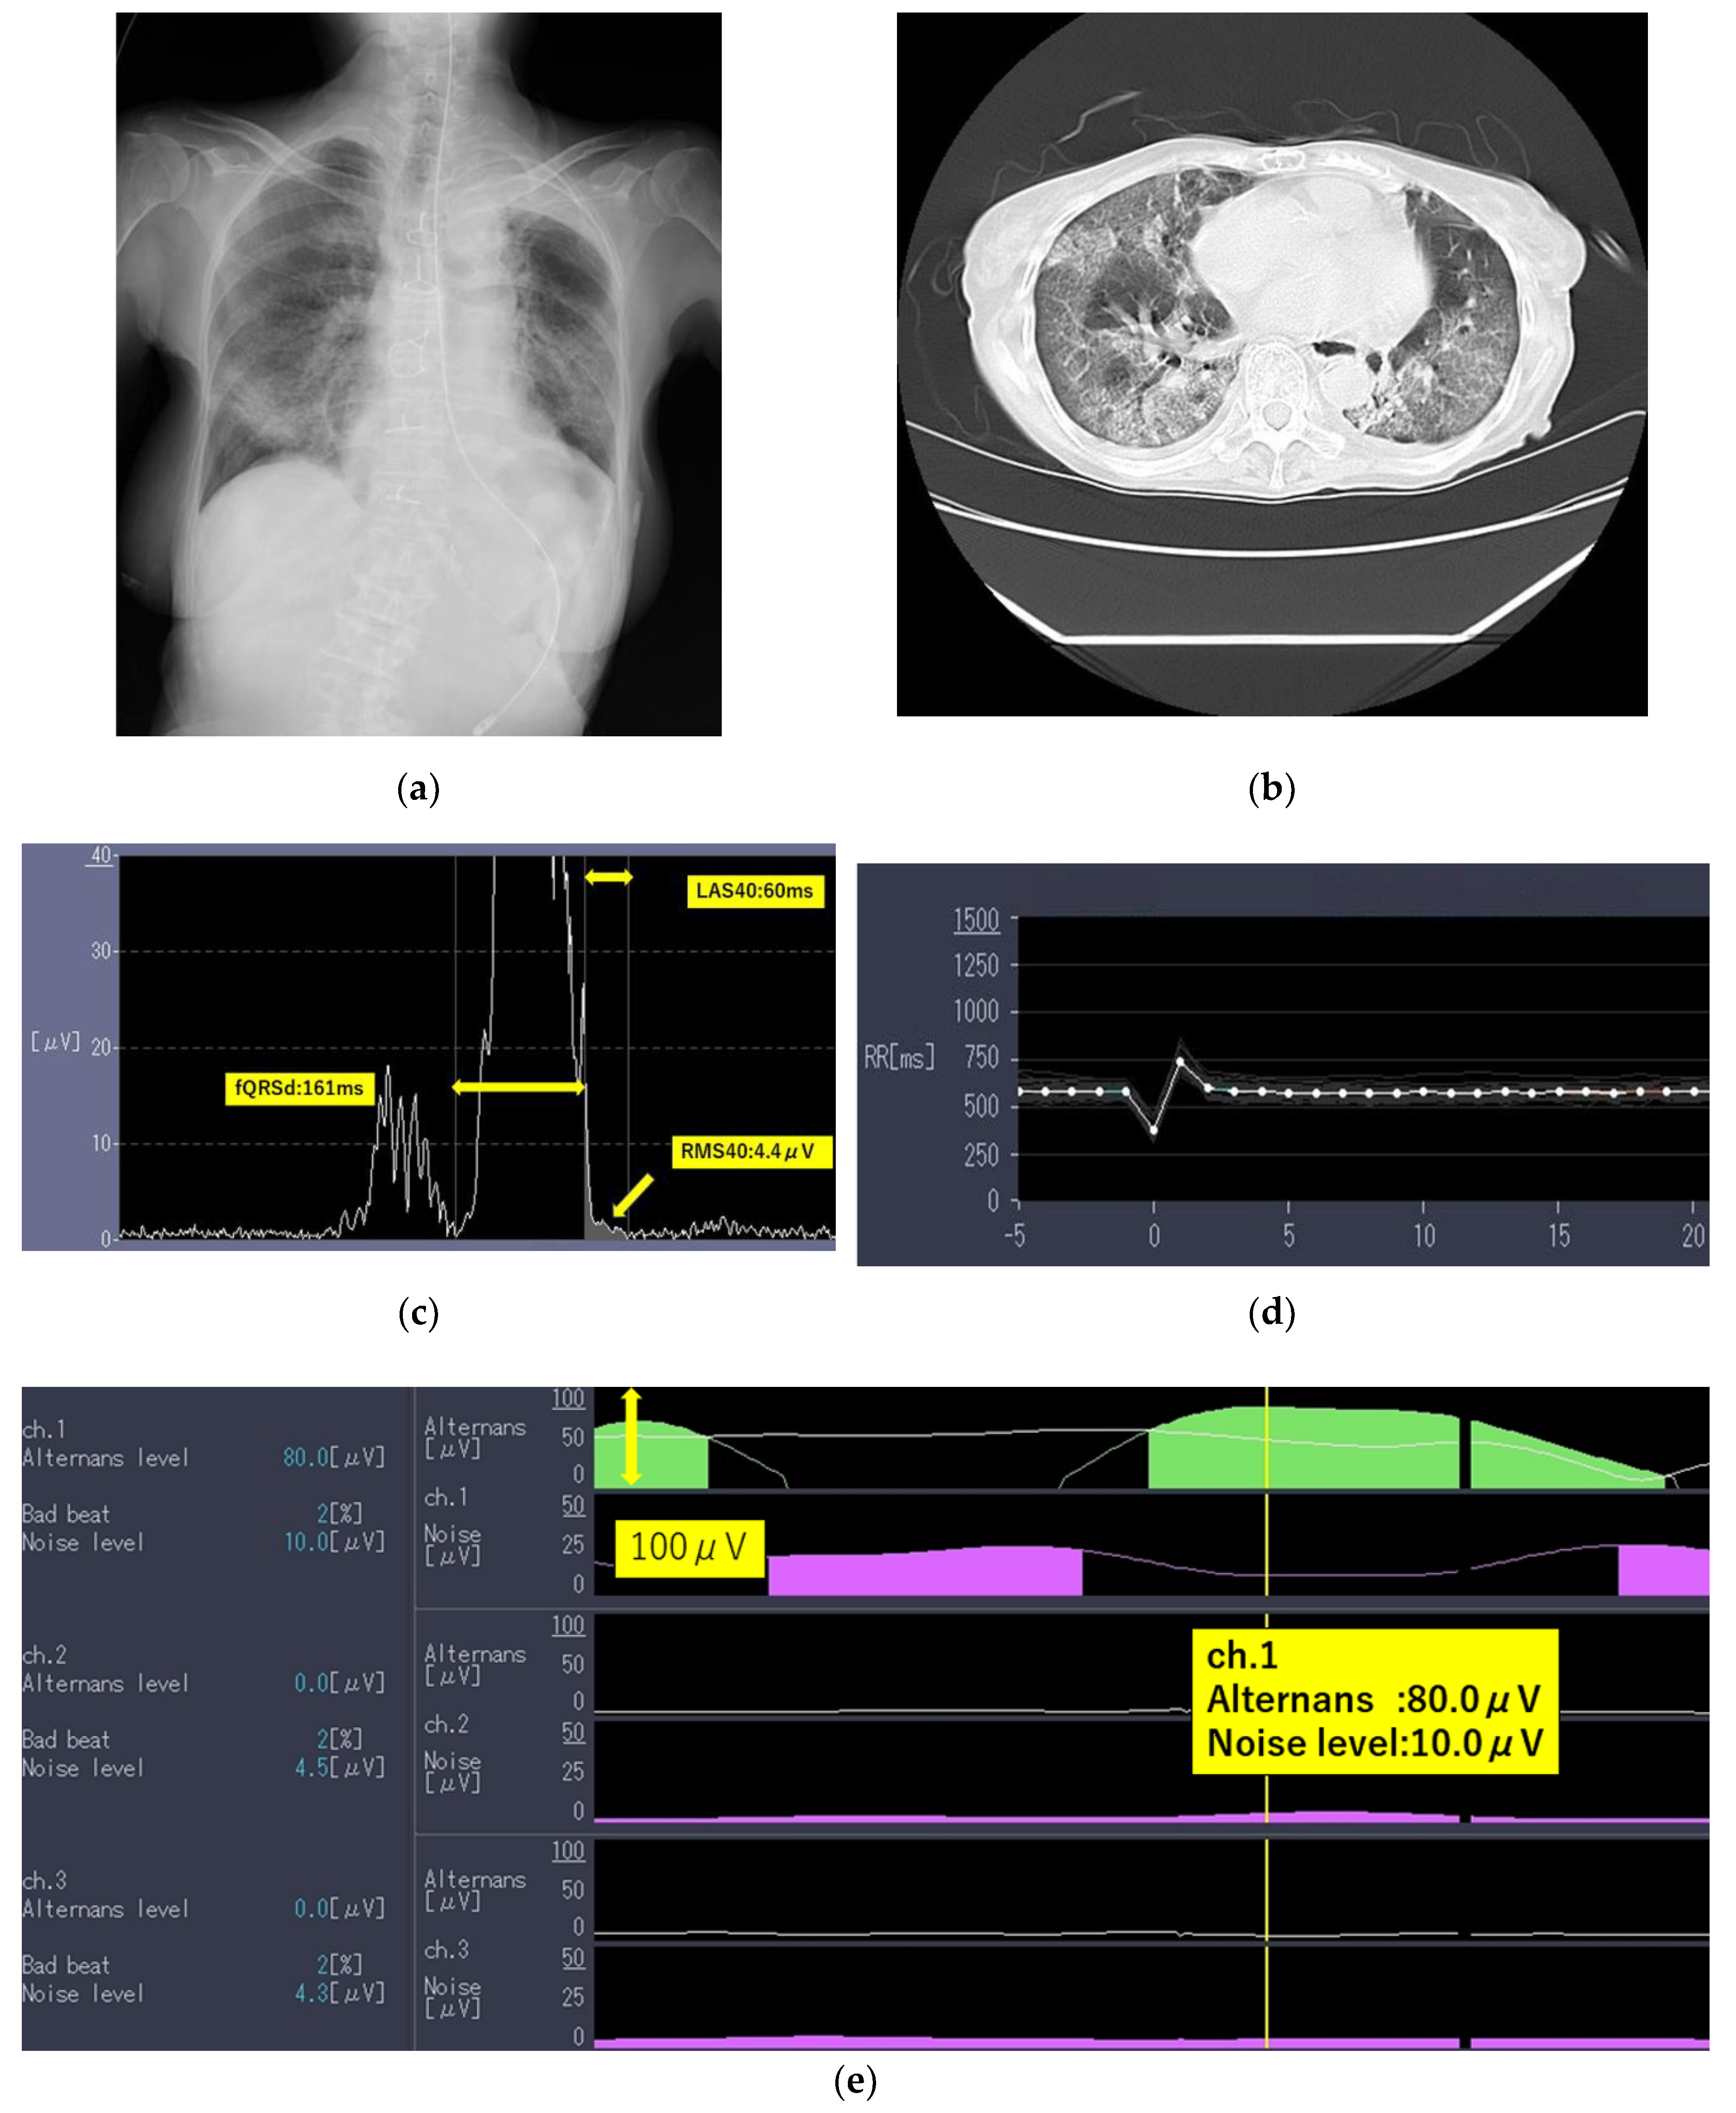

2.1. Case 1

| fQRS, millisecond | >135 | 128 | 136 | 160 |

| RMS40, μV | <20 | 4.4 | 1.5 | 10.4 |

| LAS40, millisecond | >38 | 60 | 53 | 57 |

| Determination | Positive | Positive | Positive | |

| Noise level, mV | (*1), (*2) | 10.0 | 9.6 | 12.3 |

| TWA, μV | (*1), (*2) | 80.0 | 28.4 | 35.7 |